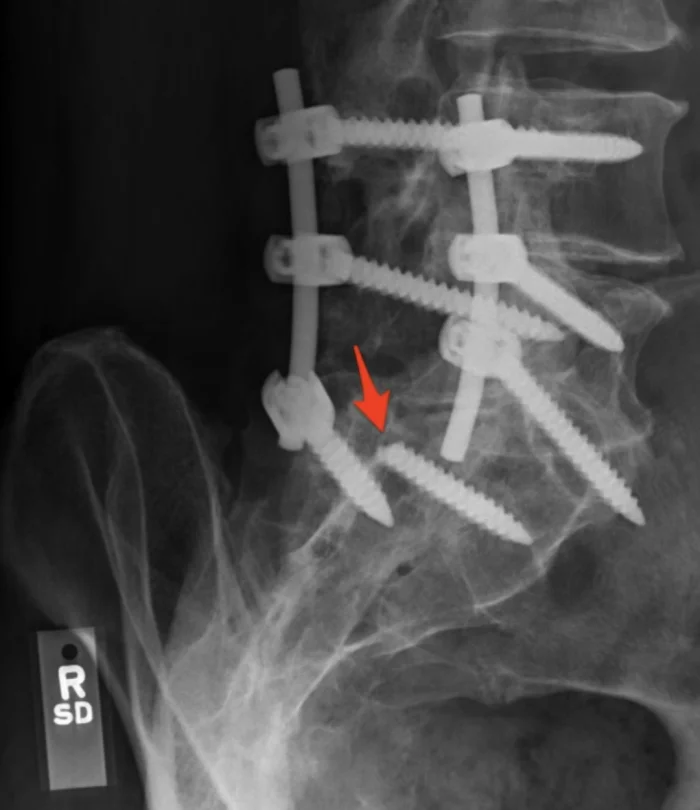

7. Мне 28 лет, я неудачно чихнул и повредил спину

9. Один из винтов, которые удерживали позвоночник, сломался. Опять операция